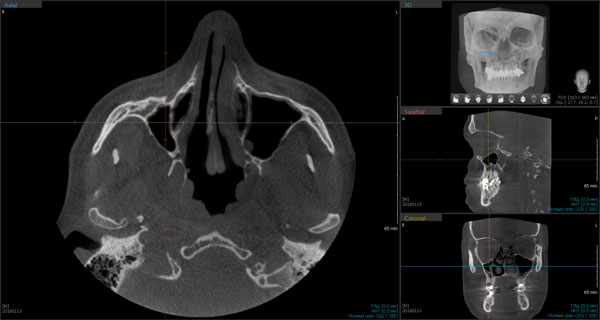

Так, например, гипоплазированные верхнечелюстные пазухи часто создают условия для развития патологических процессов, что особенно важно при подготовке имплантации в сегменте 15-17; 25-27 отсутствующих зубов. Такая рентгеноанатомия может являться следствием радикальной гайморотомии по Колдуэллу-Люку или быть врожденной гипоплазией. По данным конусно-лучевых томограмм обнаруживаются изменения топографических соотношений синуса и окружающих его структур. При измерении стенок верхнечелюстной пазухи отмечается высокая степень их толщины. Медиальная стенка при склеротическом типе строения пазухи имеет форму дуги, при этом выпуклость направлена к перегородке носа. Естественное соустье находится при таком типе строения в задней части этой аркады. Такая анатомическая специфика лучше выявляется на аксиальных компьютерных томограммах (Рис.2).

Рис.2 Конусно-лучевая компьютерная томограмма в аксиальной проекции. П/О Ez3D-i V4.0. Гипоплазия правой верхнечелюстной пазухи после проведения радикальной гайморотомии по Колдуэллу - Люку.